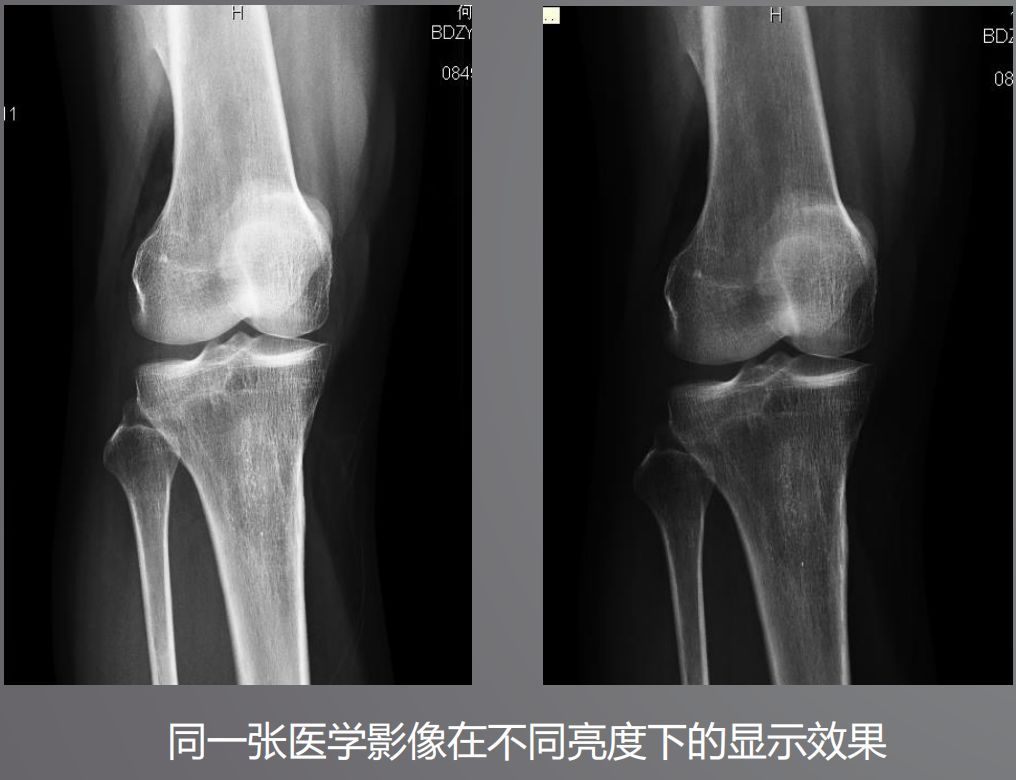

三、高亮度

高亮度從字面上就非常好理解了,回想在傳統(tǒng)膠片時代,閱片都是直接夾在大大的發(fā)光白板上。而平時我們?yōu)g覽網(wǎng)頁或者看視頻并不需要那么高的亮度,導(dǎo)致普通顯示器亮度偏低,達不到醫(yī)用閱片的標準。

根據(jù)DICOM Part14規(guī)定,所有醫(yī)學(xué)顯示器必須符合GSDF的標準,確保顯示區(qū)域亮度符合一致性。而普通顯示器是不需要刻意符合這個標準的。

醫(yī)用顯示器通過系統(tǒng)測量和調(diào)整每一個像素的亮度,降低中心和角落之間亮度和色彩的不均勻性,通過減少這些差異,確保顯示器每個顯示區(qū)都能符合DICOM GSDF標準。